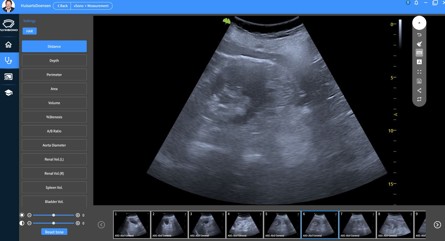

Uw huisarts is tevens opgeleid )* om eventueel, bij bepaalde klachten, een aanvullend echografie-onderzoek op de praktijk te doen. Dit zal nooit een totale buikecho vervangen, maar kan een richting geven in de beslisboom van de huisarts. Er zijn voor u geen kosten aan verbonden.

)* Nederlands Instituut voor Echografie in de 1elijn (NT-e).